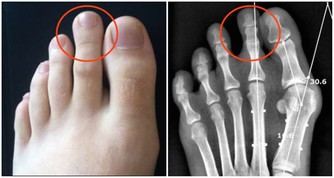

*****腎怕“1字”*****

中醫認為,腎是“先天之本”,先天之精易耗難成。因此,腎最怕的其實是“ ”。

生活中的行為、活動,既需要靠體內陽氣提供能量和動力,也需要體內的陰精提供物質給養。

如果長期“過勞”,且得不到及時的修復和養護,會導致動力系統的效能降低,腎陽耗損,腎自然就傷了。